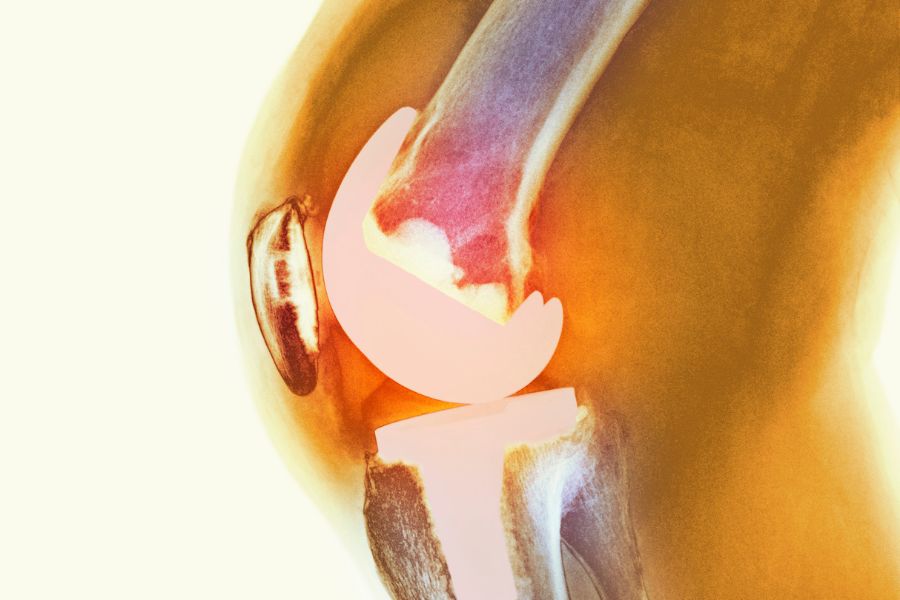

Doç. Dr. Tunay Erden, spor yaralanmaları ve protez cerrahisi alanlarında uzmanlaşmış ortopedi ve travmatoloji cerrahıdır. Özellikle ön çapraz bağ (ÖÇB/ACL) ve arka çapraz bağ (AÇB/PCL) rekonstrüksiyonu, menisküs yırtıkları, kıkırdak hasarı, çoklu bağ yaralanmaları ve kompleks diz cerrahisi konularında ileri düzey deneyime sahiptir.

• Spor ve Diz Yaralanmaları

Sporcularda sık görülen yaralanmaların (menisküs yırtıkları, ön ve arka çapraz bağ (ACL) yaralanmaları, iç ve dış yan bağ yaralanmaları, kas ve tendon) tanı ve tedavisini en güncel bilgi ve yöntemlerle gerçekleştiriyoruz

Kalça ve Diz Protezi Cerrahisi

Osteoartrit ve diğer dejeneratif eklem hastalıklarında, fonksiyon kaybını en aza indirmek amacıyla hastaya özel planlama ile gerek robotik ve gerekse klasik yöntemlerle kalça ve diz protez cerrahileri uyguluyoruz.